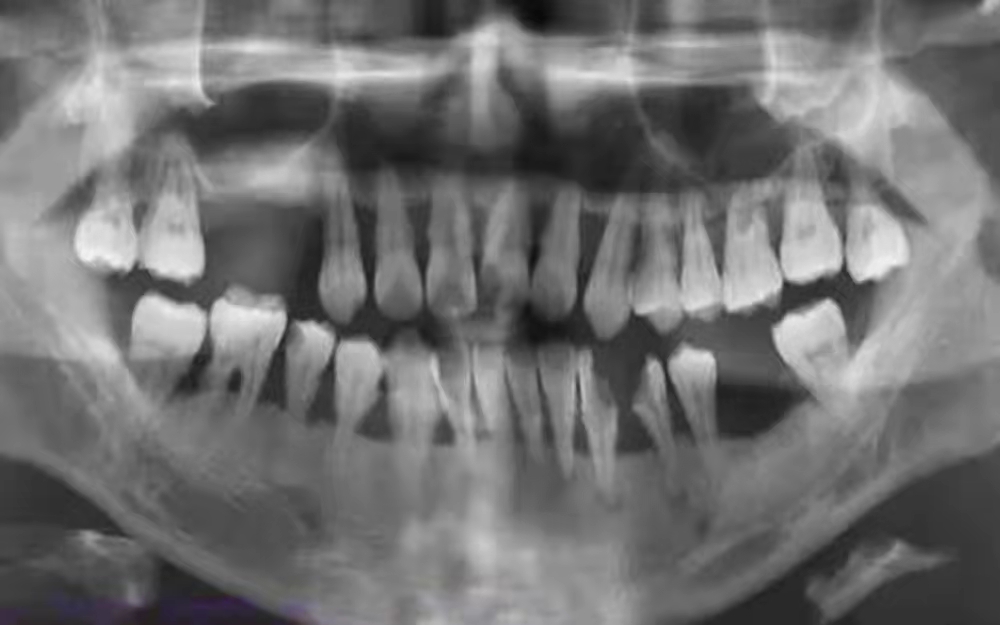

缺牙后会引起咀嚼困难,影响人的正常生活,因此往往需要找牙医去装牙,但是很多情况下牙医都会建议先把有问题的牙齿进行一下治疗,无法治疗的牙齿需要拔除再装牙,就如造房首先需要打好地基才能使房屋使用的不出问题,使用的年代久远。临床上哪些牙齿在装牙前必须要拔除呢?

严重蛀牙导致的残根残冠

也就是那些由于龋坏没有及时治疗的牙齿,大部分的牙齿组织都被破坏了,只留下破烂不堪的牙根或者牙齿空壳,这种牙齿烂到了根部无法直接修补,由于牙根炎症等感染反复发作,而引起全身其他疾病,如风湿性心脏病、肾炎、视神经炎,而且残根残冠的边缘往往比较尖锐,是口腔癌如舌癌、牙龈癌、颊癌的重要病因,就应拔掉。

牙周炎导致过度松动的牙

这种常见于老年人,由于口腔卫生不良,牙结石过多没有及时清理,长期的炎症刺激使得牙齿周围的骨头一点点被破坏,甚至最后牙根都漏出来了,牙齿也是左摇右摆的,这时候就没有挽救的机会了,牙齿周围慢性炎症还会使牙齿周围的牙槽骨逐渐吸收掉,不仅影响邻近的牙齿,还造成牙槽骨的高度降低、厚度变薄,到了一定程度,再装牙就很难了。尽早拔除反而可以减缓牙齿周围骨头的吸收,为将来做假牙留条后路。

引起局部或全身疾病的病牙病灶牙

由于牙齿根部或者周围病灶发展,导致局部骨髓炎等,或者感染扩散全身,这种牙就应该尽快拔除。

移位和错位的牙齿

会影响到假牙的就位和使用,造成假牙无法佩戴。